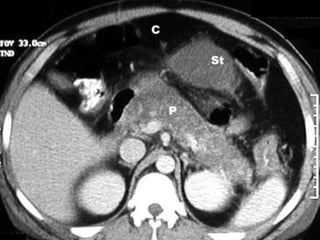

 Abdomen (cholecystitis, pancreatitis, aortic

aneurysm, peptic ulcer disease, nephrolithiasis,

pelvic inflammatory disease, diverticulitis)

Pancreatitis